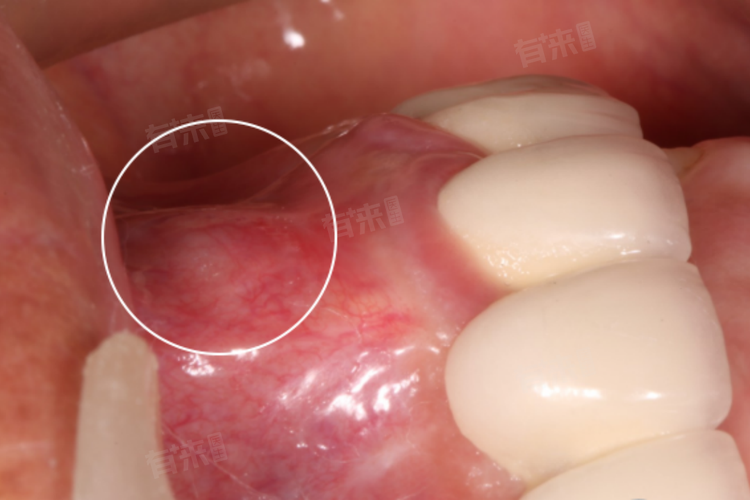

2、牙龈变化

牙龈会出现明显的红肿,炎症聚集在根尖部位,导致牙龈局部组织充血、水肿。随着脓肿的形成,牙龈上可能会鼓起脓包,用手按压时有波动感,脓包破溃后会有脓性分泌物排出,这表明炎症已经发展到一定程度,需要尽快处理。